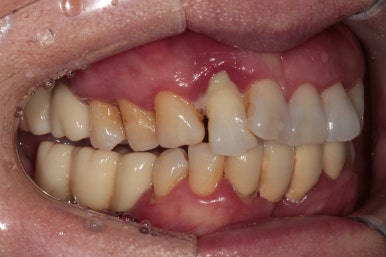

50대 여자 환자분입니다. 처음에 내원하셨을 때 정면 사진이에요.

딱 보아도 잇몸 상태가 참 좋지 않았습니다. ㅠㅠ 특히 위 앞니는 가만히 있어도 고름이 나오고 있는 상태지요..

고개를 좌우로 돌려 좌측과 우측을 살펴보았습니다.

제가 앞에서 본다고 생각하시면, 왼쪽 사진이 우측이겠지요?

우측 가쪽 앞니 (측절치)에서 active하게 농양이 나오고 있는 것을 보실 수 있어요.

당연히 위턱 앞니들이 모두 흔들흔들 합니다.